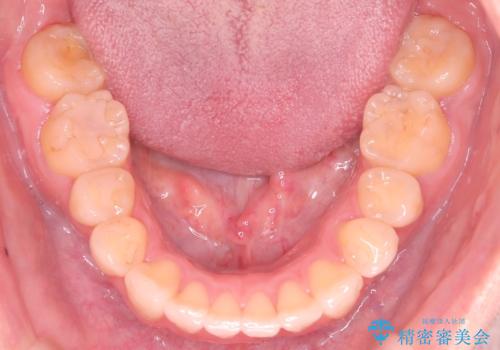

- 前歯の凸凹と口元の突出感を主訴に来院されました。

臼歯関係が上顎前突傾向のため、上の小臼歯を抜歯してワイヤー矯正を行なっております。

下顎の叢生はIPRを行なって配列しています。